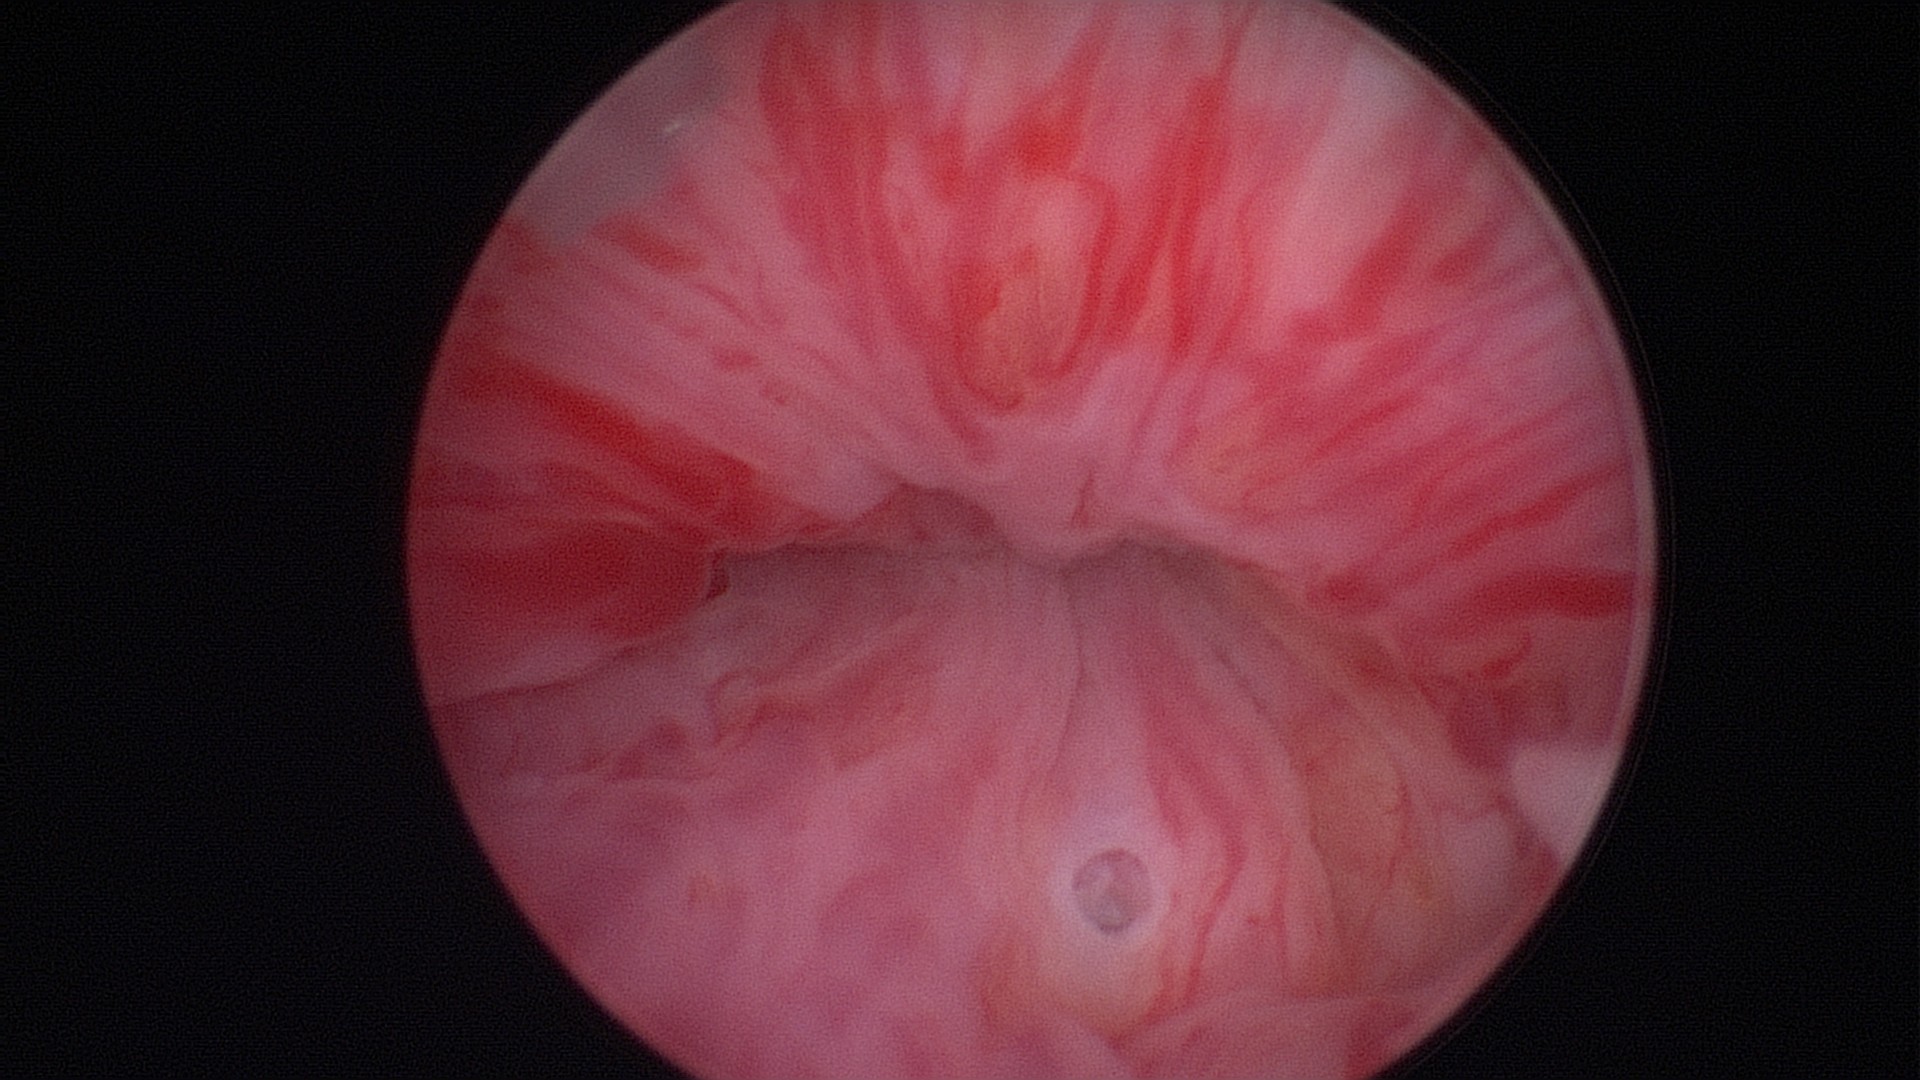

Final image of the mid-urethra after creating four depots of Bulkamid® at the 12, 3, 9 and 6 o’clock positions.